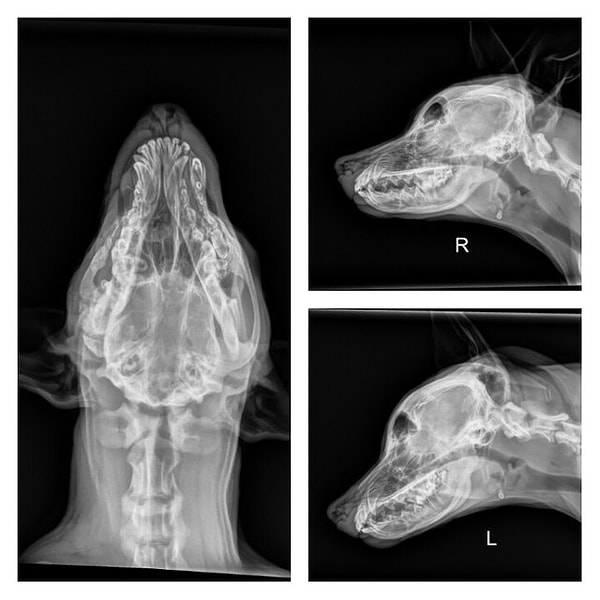

Результаты более детального обследования Скуиша очень удивили ветеринаров, потому что все те травмы, полученные 4-месячным щенком, были вовсе не укусом другого животного!

Увидев в черепе и правой верхней челюсти серьезные переломы, команда не нашла подобных травм остальных частей его тела. Это показало, что кто-то намеренно бил Скуиша по голове. Пес был изуродован «человеком»...